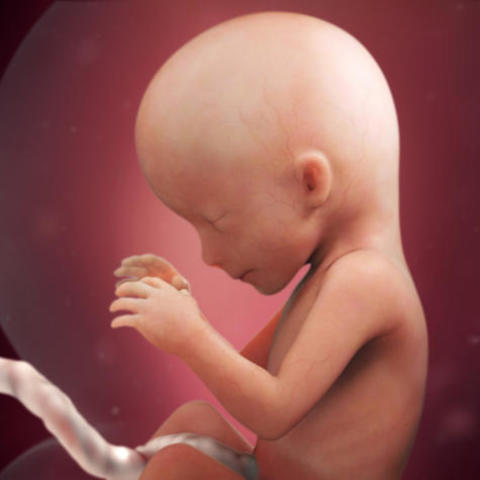

• development at 28 weeks

development at 28 weeks

bay weighs about 2 pounds 6 ounces and changes position often at the point of your pregnancy.